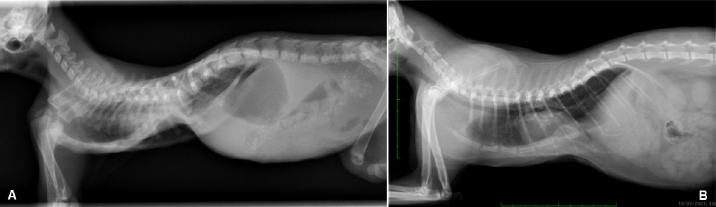

Radiographic examination revealed severe dorsal displacement from the fifth sternebra to the xiphoid cartilage and a dorsal displacement of the cardiac silhouette on the lateral view (Fig. 1A), and a left mediastinal shift and compression of the left pulmonary lobes on the ventrodorsal view (Fig. 2A). VI and FSI were measured on the radiographs, being 3.2 and 9.1, respectively. The authors decided to measure these two indices also at the level of T9 because this vertebra corresponded to the point of minimum height of the thorax. VI and FSI at the level of T9 were 2.3 and 15.2, respectively. The authors measured also the minimum thoracic height (MinTH) that resulted 4.3 mm, at the level of the last sternebra.

Fig. 1. Left lateral radiographic view of the thorax of the cat with pectus excavatum. Comparison of patient’s thorax before (A) and after (B) surgical treatment at 9 months postoperatively.

Fig. 2. Ventrodorsal radiographic view of the thorax of the cat with pectus excavatum. Comparison of patient’s thorax before (A) and after (B) surgical treatment at 9 months postoperatively.

Radiographs were obtained as previously described at each follow-up examination (Figs. 1B and 2B). IV, FSI, and MinTH were calculated and the values are reported in Table 1.

Four months postoperatively the kitten increased her body weight from 550 to 2,436 g and the skeletal deformity was dramatically improved at physical examination. No episodes of dyspnea or exercise intolerance were noticed by the owner. The VI and FSI measured on the radiographs obtained 4 months after surgery were 10.2 and 2.0, respectively. The same indexes measured at the level of T9 were 8.8 and 2.3, respectively, and MinTH was 21 mm.

Nine months postoperatively the cat underwent an ovariohysterectomy with no anesthetic-related complications. The cat was discharged from hospital 6 hours postoperatively and recovered uneventfully. Radiographs were obtained as previously described before the surgery. VI and FSI resulted in 12.4 and 1.5, respectively; the same indexes measured at the level of T9 were 9.4 and 2.1, respectively, and MinTH was 26 mm.